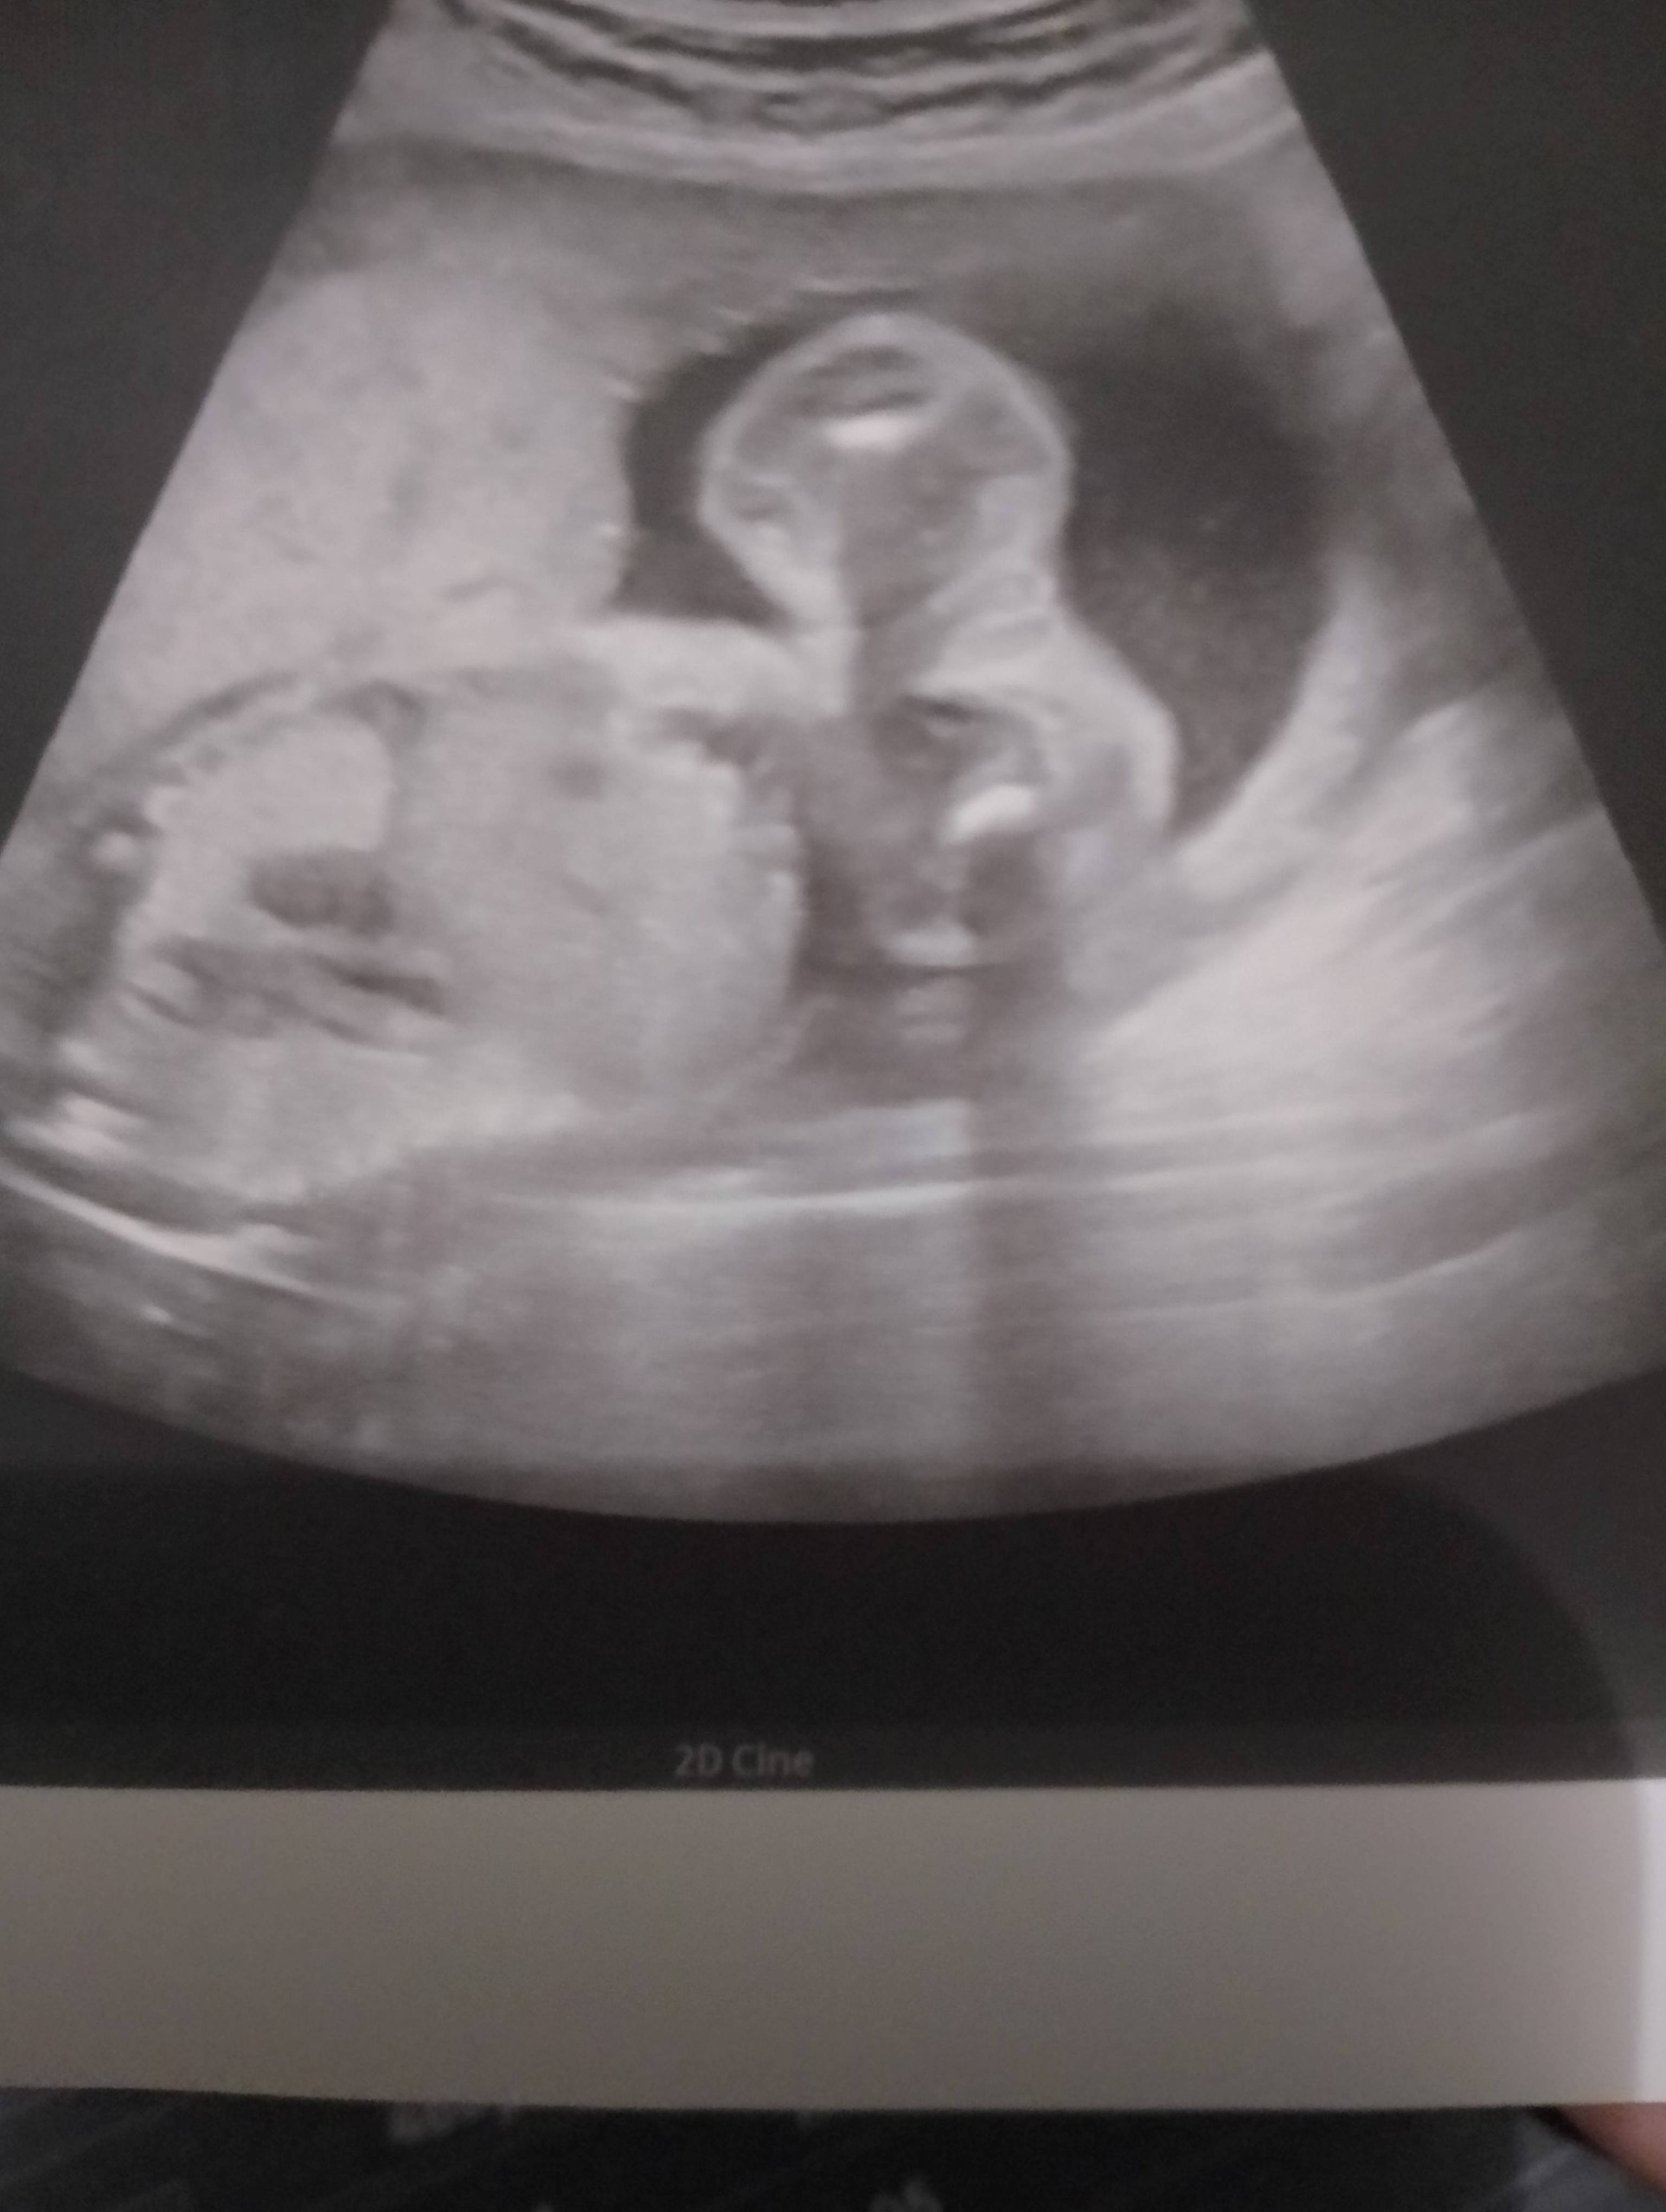

U mnie w tym tygodniu też mówił że chłopaczek bo widział siusiaka więc może być tak jak mówisz z tym przerośnieciem bo teraz jak byłam w 19tc widział dziewczynkę 🫣 Czekamy na połówkowe 30.01 może się potwierdzi 🥰

• IMG_20240109_110929.jpg

IMG_20240109_110929.jpg

872,9 KB · Wyświetleń: 125

Tu to Ewidentnie jest dziewczynka :) tyle co ja już tych zdjęć przejrzałam. Widać odrazu